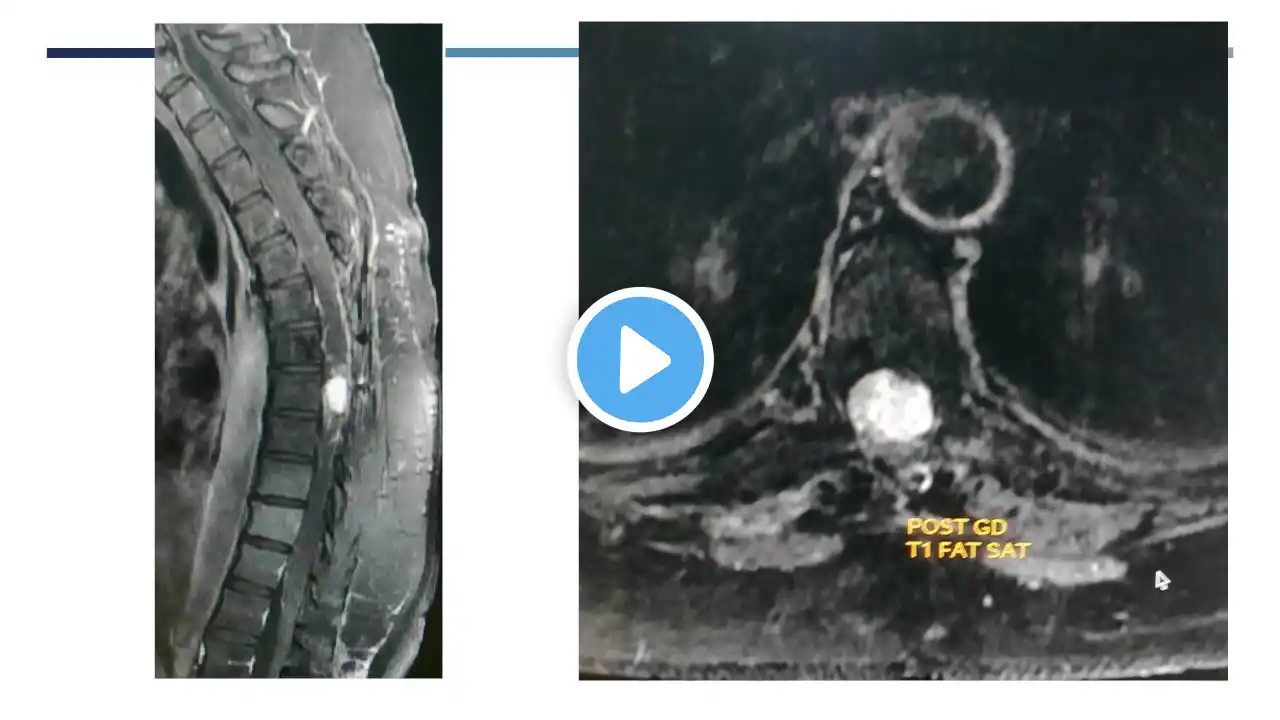

This is a short video compilation of images and angiographic runs showing a case of endovascular embolisation of a large sacral schwannoma, done before surgery. This helps in decreasing the blood loss, decreases the operative time and improves chances of complete removal without complications. | AIIMS Patna | Interventional Radiology